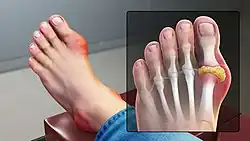

Gout is a form of arthritis caused by excessive uric acid production, resulting in urate crystals depositing in joints, particularly in extremities, such as toes.[48][49] Urate levels in the blood may increase from consuming purine-rich foods or from body factors affecting urate clearance from the blood, a topic remaining under study.[48]

Gout

In the early stages of gout, usually only one joint is affected; however over time, many joints can become affected. Gout most commonly occurs in joints located in the big toe, knee, and/or fingers.[49] During a gout flare, the affected joints often become swollen with associated warmth and redness. The resulting pain can be significant and potentially debilitating.[71] When one of these flares occurs, management involves the use of anti-inflammatories, such as NSAIDs, colchicine, or glucocorticoids.[72] In between gout flares, it is recommended that patients take medications that decrease the production of uric acid (i.e. allopurinol, febuxostat) or increase the elimination of uric acid from the body (i.e. probenecid).[72][73]